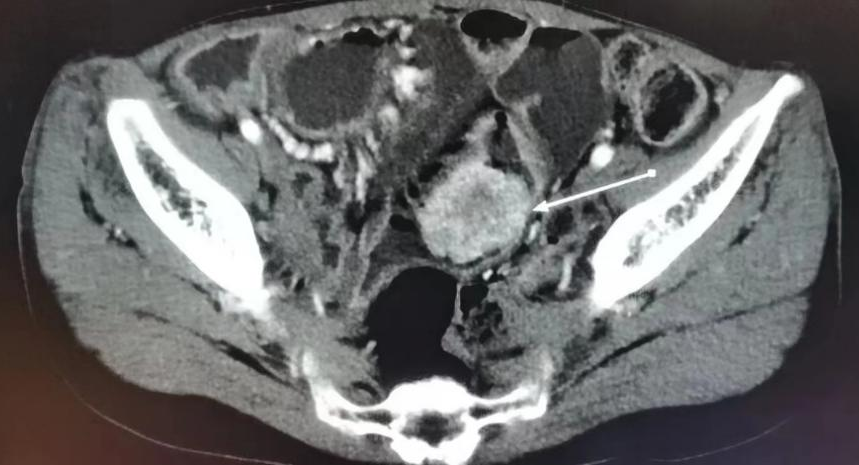

而根据周女士情况,CT影像显示小肠末端有巨大占位,息肉直径约8*5cm,由于多次手术已经造成肠粘连,同时伴随肠套叠症状,常规切除方法都不能安全有效地解决问题。根据中国小肠镜诊治Peutz⁃Jeghers综合征的专家共识意见(2022年),对于直径>5 cm的小肠巨大息肉,尤其伴有小肠套叠时,内镜下治疗发生出血及穿孔等严重并发症的风险相应增高,需在充分权衡利弊后慎重选择治疗方式。内镜中心主任周平红教授带领团队一起讨论周女士的治疗方案,虽然手术难度极高,目前国内外相关手术经验较少,但在多年积累的丰富经验和内镜下切除先进技术的支持下,内镜团队在做足了充分准备的前提下,决定再闯禁区,为周女士行小肠镜下巨大息肉切除术。